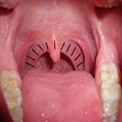

Wichtig: Fassen Sie den Tupfer nicht vorne an. Bild 1 - Sehen Sie sich im Spiegel die anatomischen Gegebenheiten im Rachenraum an. Die im Bild schwarz schraffierte Fläche ist das Zielgebiet Ihres Abstrichs. Bild 2

Bild 2